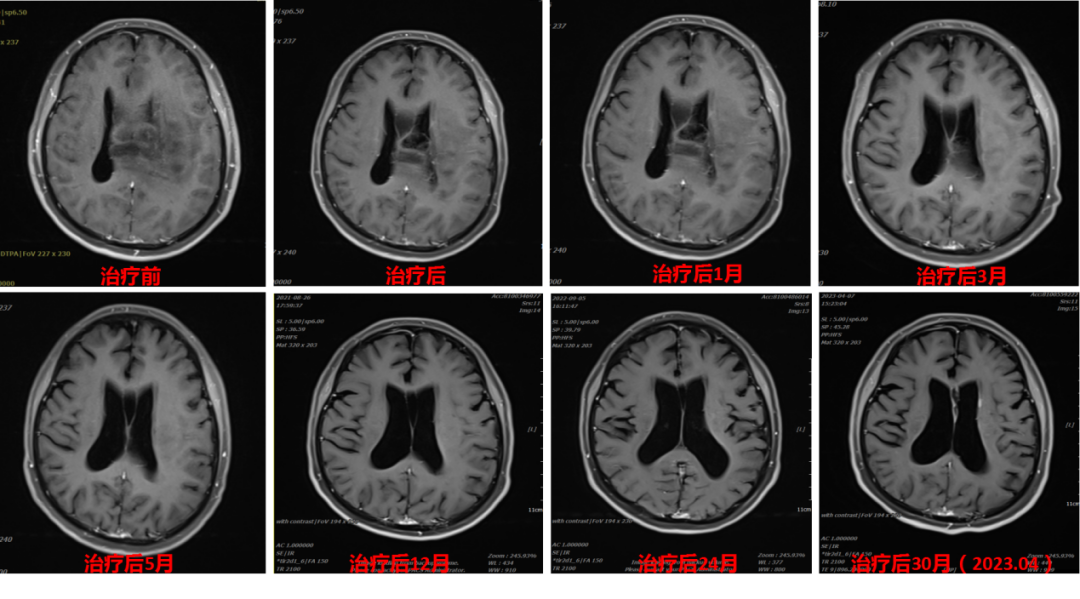

2019年,42岁的杨女士不幸被脑胶质瘤“击中”,犹如晴天霹雳一般,辗转多家医院后在天坛医院确诊为脑胶质瘤,因位置特殊,无法进行手术切除。得知这个消息后杨女士心情低落,寻求最佳治疗方法。2020年5月,杨女士多次出现癫痫,复查后得知肿瘤较前增大,脱水、抗癫痫治疗后症状仍不能缓解。不能做手术,肿瘤长在脑袋里面就像一个定时炸弹,杨女士和家人每天提心吊胆,多番上网查询相关资料,周围的亲戚朋友也在多方打听脑胶质瘤最先进的治疗办法,终于他们看见了有关武威重离子中心的报道,咨询后可以进行重离子治疗,这让杨女士瞬间燃起了生命的希望!2020年6月,杨女士毅然决然的来到我中心,在我中心多学科联合会诊后进行了20次碳离子治疗,治疗期间无任何不适,且未发生过癫痫,治疗结束后肢体无力症状完全缓解,病灶也较前明显缩小。杨女士非常高兴地将每次随访的资料邮寄我科,今天我们收到了治疗结束后30个月的随访资料,病灶已经完全消失,无任何不适,我们真替她感到高兴!

以下是杨女士碳离子治疗近30个月的影像随访资料(图1,图2)

图2